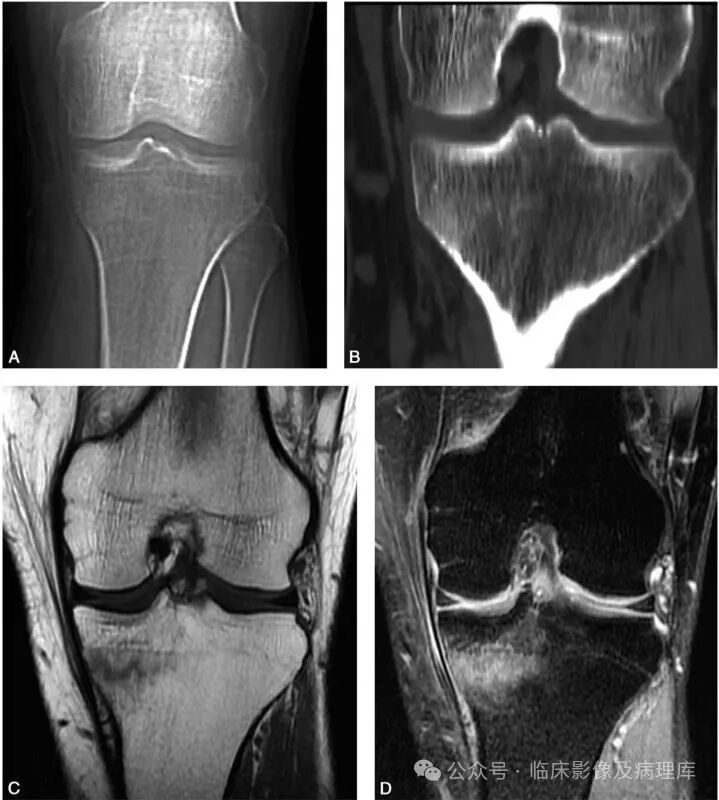

A、B.左侧胫骨正位片及CT冠状位重组像:左侧胫骨干骺端内侧骨松质区见片状骨质硬化改变,内缘皮质似不连续;C、D.左侧胫骨SE T1WI和脂肪抑制FSE T2WI:左侧胫骨干骺端内侧骨松质区见横行弯曲线样长T1信号,T2WI显示不清,周围示大片状长T1长T2水肿样信号